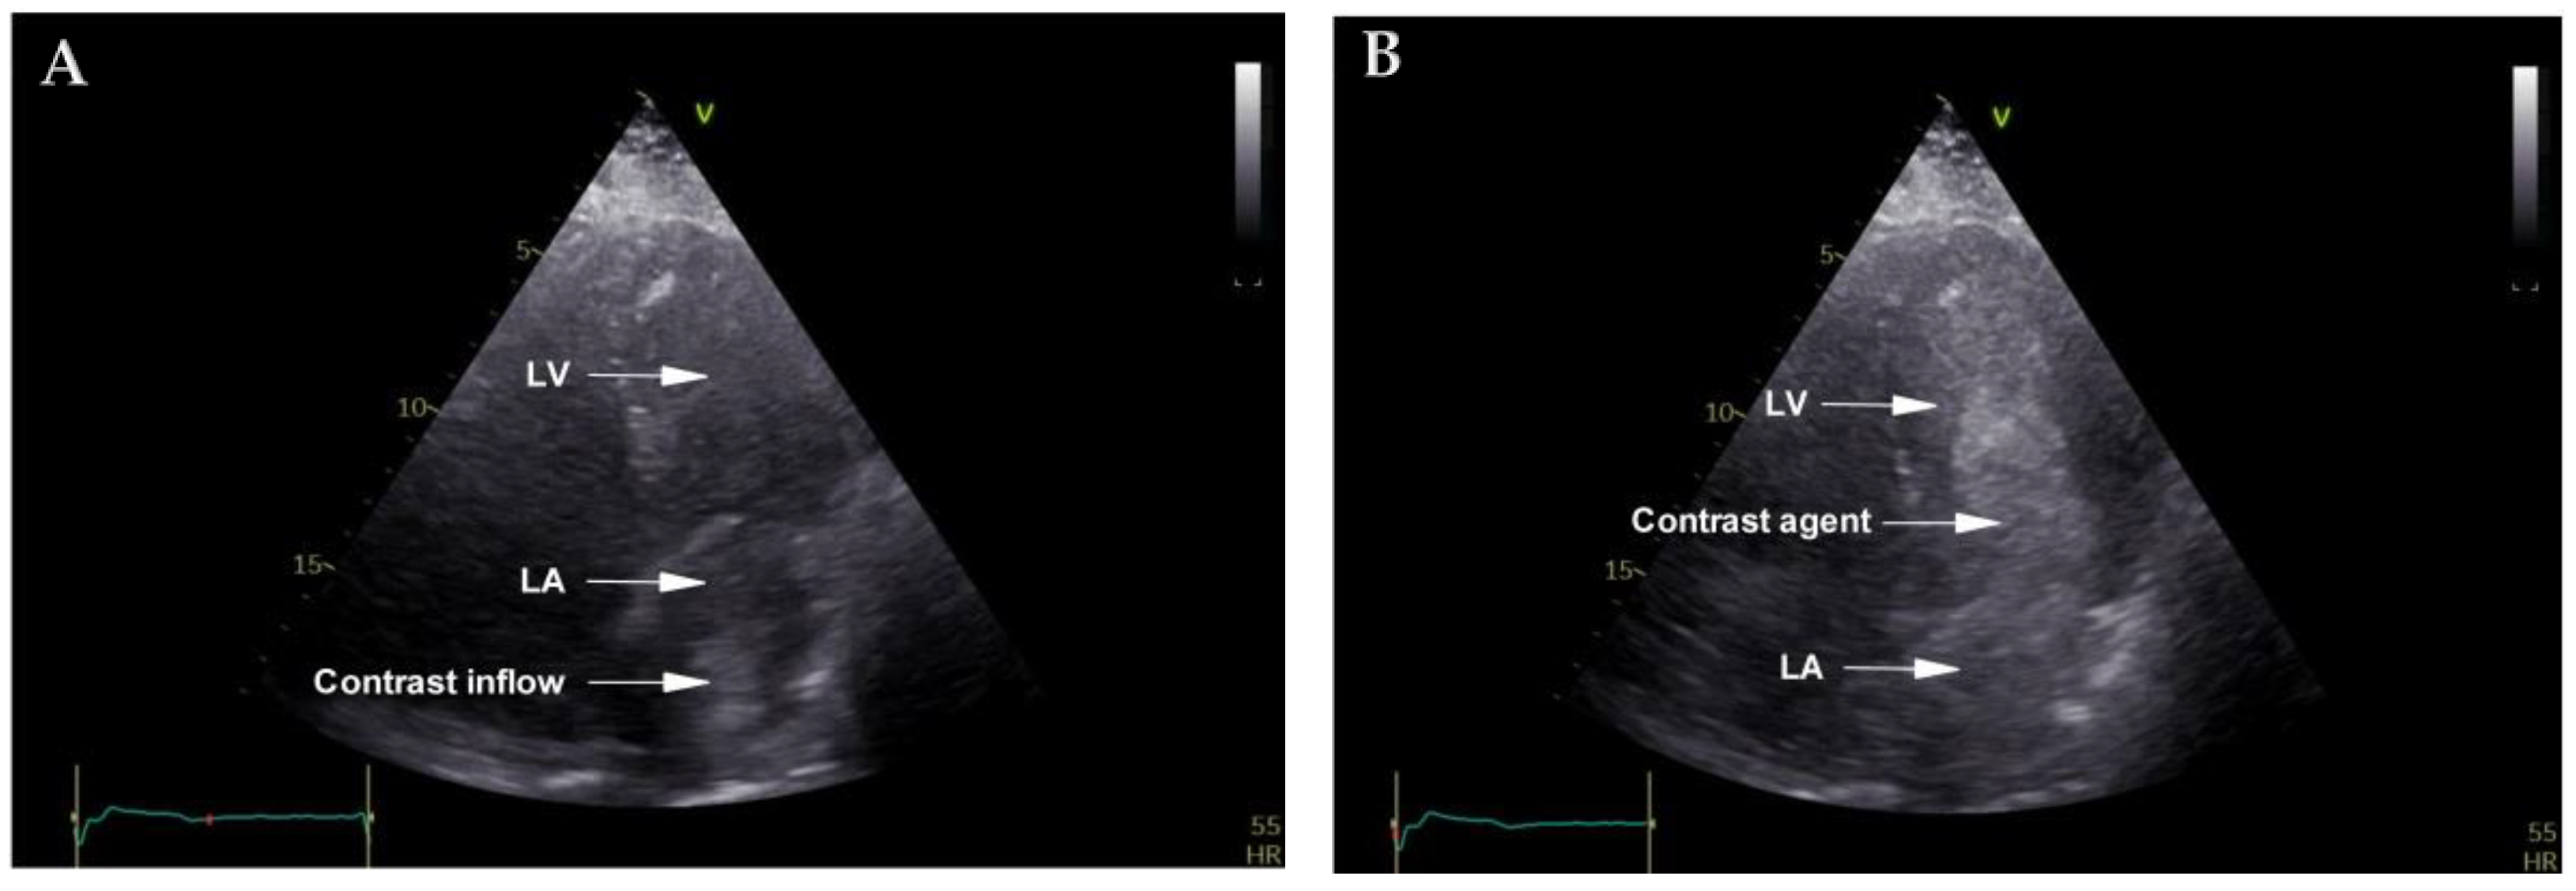

2. Case Report